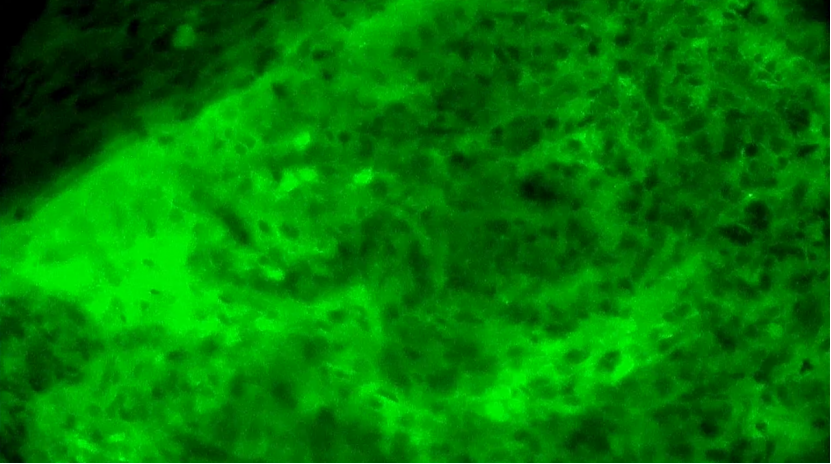

第1次掃查離體腫瘤組織,細(xì)胞核異型性明顯,分布不規(guī)則且密度高,陽性。

第2次掃查瘤腔,一處組織的細(xì)胞核異型性明顯,分布不規(guī)則,密度較高,陽性。